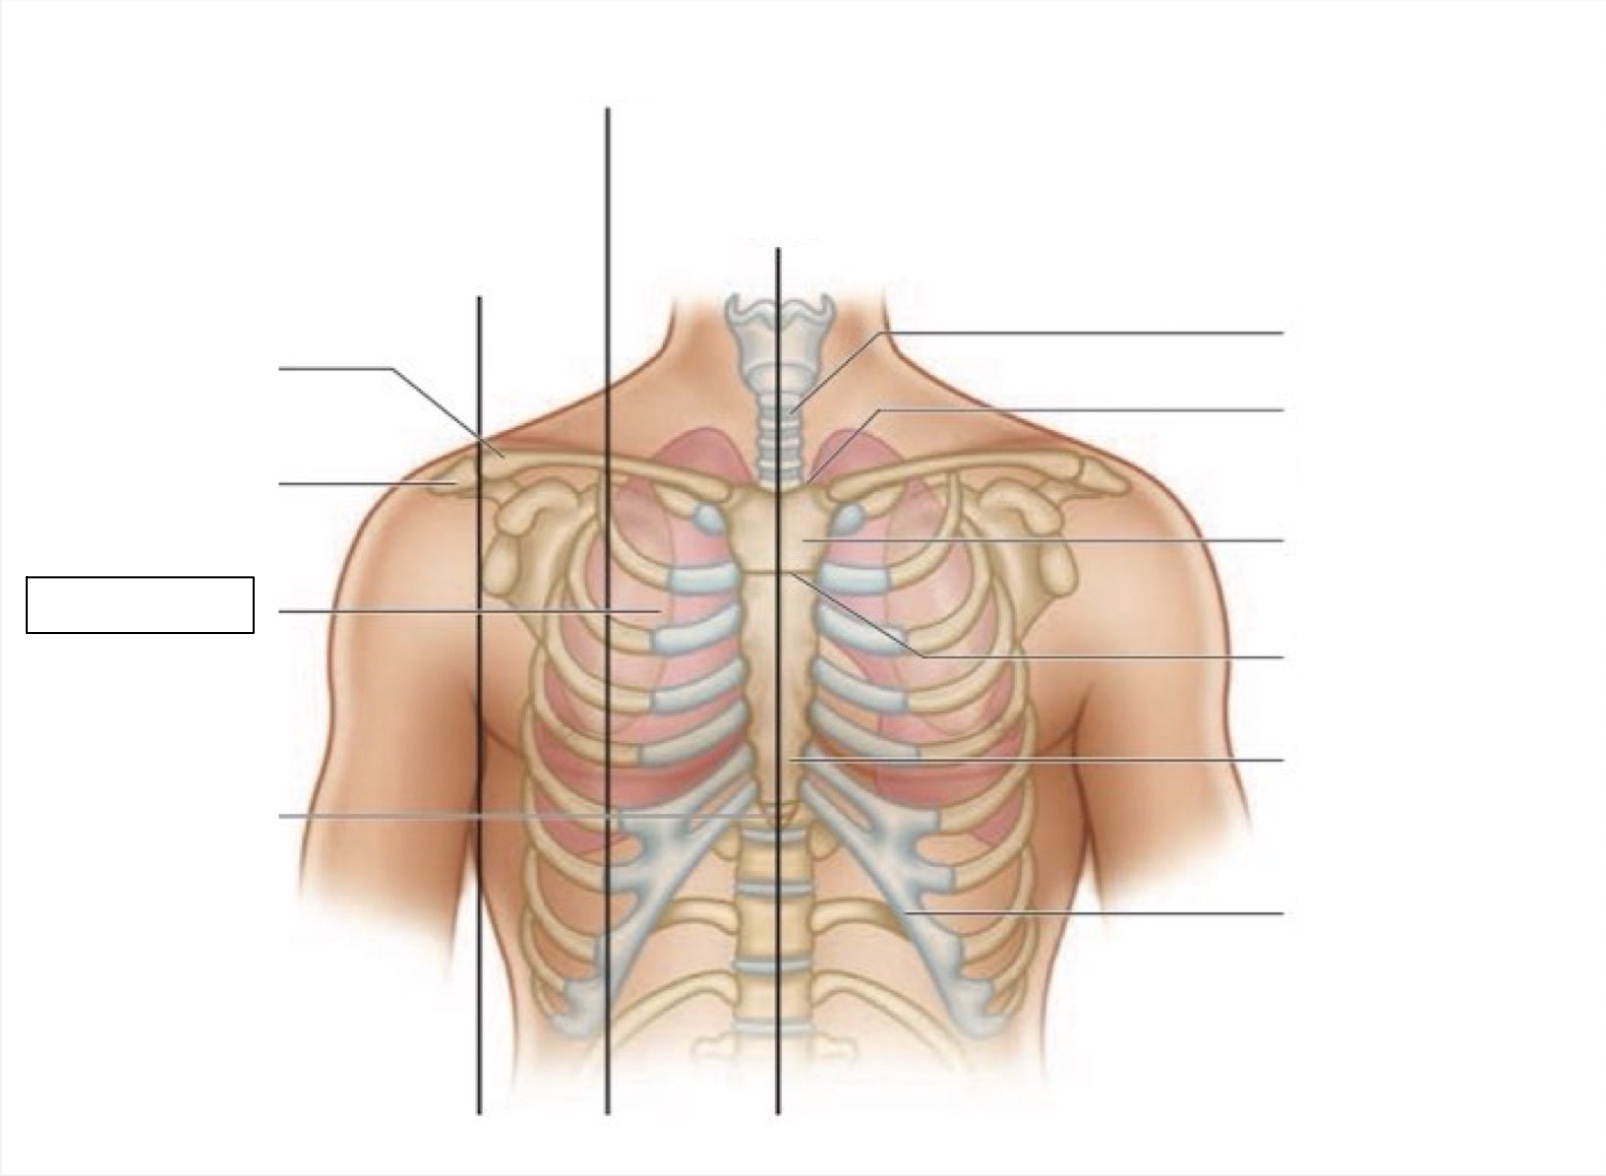

midsternal line

trachea

suprasternal notch

manubrium

angle of Louis

sternum

costal margin

xiphoid process

intercostal space

acromion

clavicle

anterior axillary line

midclavicular line

inferior angle of scapula

scapula

midscapular line

midspinal line

spinous process